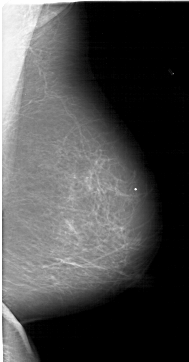

A_1513_1.LEFT_CC

LEFT_CC LINES 6586 PIXELS_PER_LINE 3421 BITS_PER_PIXEL 12 RESOLUTION 43.5 OVERLAY